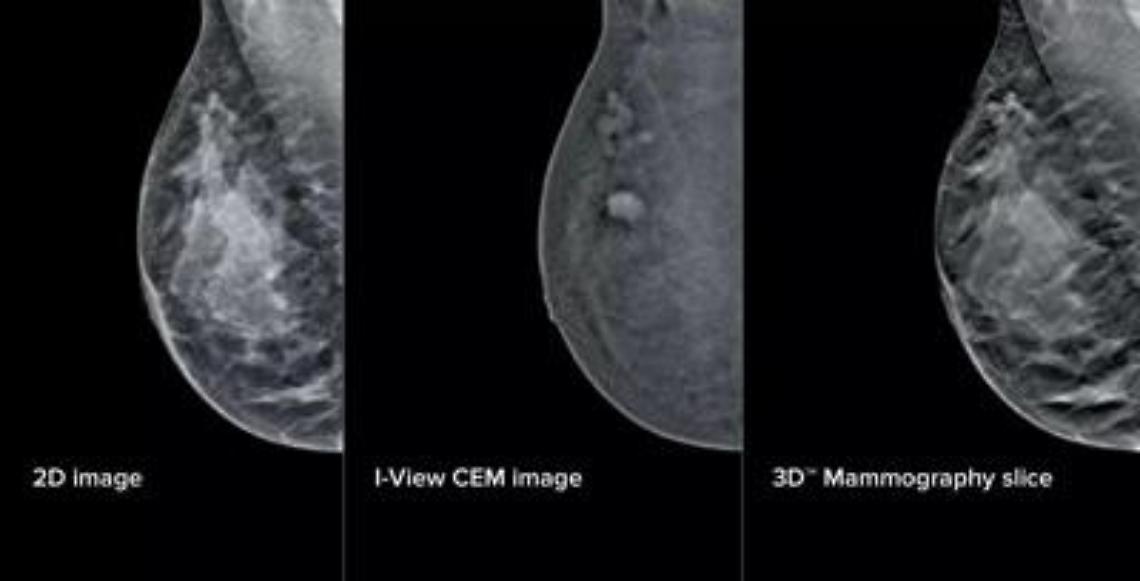

L'aggiornamento - illustra il San Camillo - si compone di elementi fisici e virtuali in due ambiti principali: la mammografia con refertazione e la biopsia mammaria. Sul fronte della refertazione, è stata introdotta una nuova workstation con monitor ad altissima risoluzione e strumenti avanzati di analisi delle immagini. Un software dedicato consente di valutare in modo oggettivo la densità del tessuto mammario, un elemento importante perché associato al rischio di tumore al seno. A questo si aggiunge un software che analizza struttura e densità del tessuto mammario, tecnologia di tomosintesi avanzata che riduce del 66% il numero di slice - le 'fettine' spesse 1 mm di tessuto mammario acquisite dal mammografo - mantenendo le stesse informazioni diagnostiche. Meno immagini da scorrere significa meno affaticamento: una riduzione del carico cognitivo per il radiologo stimata intorno al 13%, con benefici concreti soprattutto nelle sessioni di lettura multipla. A supporto dei medici - prosegue la nota - è stato integrato anche un sistema di intelligenza artificiale che evidenzia automaticamente le aree sospette sulle singole slice, come microcalcificazioni o alterazioni del tessuto, e fornisce indicazioni utili per la priorità di lettura. Studi preliminari indicano "un miglioramento della capacità di individuare lesioni fino al 9%".